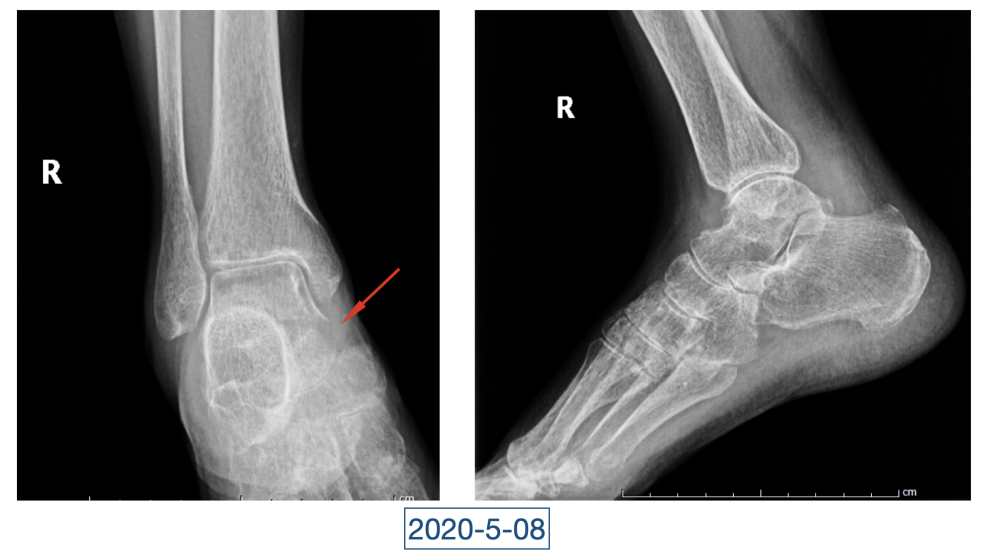

“虽说没到奄奄一息的地步,但一看就是患了大病,整个人都瘦脱相了。”李辉是西安市红会医院关节病医院病区副主任,2020年4月初第一次见到黄大娘时,他吓了一跳。黄大娘今年61岁,2019年腊月二十九,在家打扫卫生准备迎接新年的她突然开始高烧不退,腰背也痛。连夜送到当地医院补液、止疼、退烧、抗感染,一套组合拳下来烧是退了,疼痛的症状却持续在加重。从过年到正月,一直在当地医院输液、打针,黄大娘都没有好转,疼痛的地方反而越来越多。大概过半月,就多一个地方,腰、背、胸、颈部、关节、脚……此起彼伏,全身上下都觉得疼痛无比。哪里疼就去哪个科,今年四月前,黄大娘辗转多家医院多个科室寻求治疗,住院出院了一次又一次,连最高级别的抗生素都用到了,但就是没有效果。

全身上下11处骨关节被破坏!密密麻麻的诊断看得李辉毫无思绪,这么久都查不出来的病因能让他查出来吗?一时间,他也说不出话。看着黄大娘深深凹陷的双眼,浑身上下几乎看不见肉,就像罩着一层饥饿的青黄色的薄皮。过了好一会儿,他叹了口气,说:“先住下吧,用药把关节疼痛缓解一下,再想办法。”

经过科室讨论、会诊,李辉也查阅了很多资料,按照黄大娘的症状,他跟之前的接诊医生一样,觉得应该是骨关节感染。可之前的穿刺、培养各种检查也做过,为什么没有找到致病菌?李辉想,或许是检查中出现了问题,没有查对地方。于是他决定,在B超引导下骨穿刺,通过最新技术精准定位病灶,只有这样也许才能抓到真正的“罪犯”。

在黄大娘入院第四天,李辉将她推入检查室,结果很快出来了,为烟曲霉菌感染。这个结果验证了李辉的想法,也解释了此前抗感染药物为何一直不奏效。“找到元凶就好办了,对症用药就可以。真菌感染本来治疗时间就很长,骨科类感染灶治疗时间更长,用了5个月的时间,终于治好了。”

近日随访得知黄大娘身体好转,李辉脸上的笑容掩饰不住,他说,据查阅文献,11处感染灶,这是全世界感染灶最多的骨关节感染,但现在,这罕见、复杂的病已经被治愈。